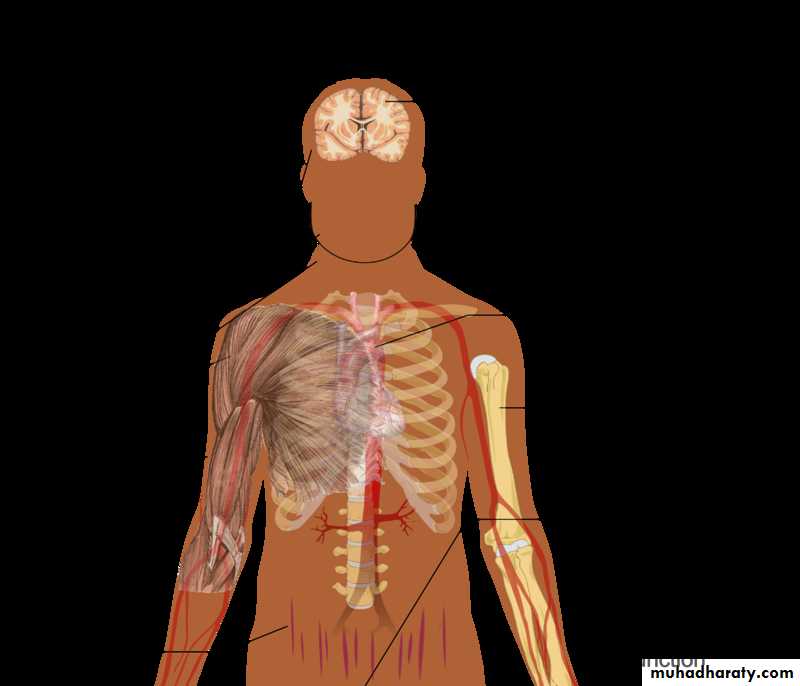

The adrenal glands

The adrenals are pair of glands of about 4 grams situated at the upper poles of kidneys in the retro peritoneum within Gerota’s capsule.

The arterial blood supply from the aorta, phrenic and renal arteries. A large adrenal vein drains on the right side into the inferior vena cava and on the left side into the renal vein.

There are two distinct components of the gland the inner adrenal medulla which is a mesodermal cells and the outer adrenal cortex which is a neuroectodermal cells.The cortex is under control of ACTH from the pituitary gland which is under control of hypothalamic CRH.

The adrenal cortex compsed of 3 zones

The outer zona glomerulosa produce aldosterone, that regulates sodium–potassium homeostasis .The zona fasciculata produce Cortisol that has numerous metabolic and immunological effects.

the inner zona reticularis produce adrenal androgens dehydroepiandrosterone (DHEA). Responseble for secondery sexsual criteria.

The adrenal medulla consists of a thin layer of large chromaffin cells, which store catecholamine granules. It activate the cardiovascular system, resulting in increase blood pressure and heart rate; vasoconstriction of i the splanchnic vessels and vasodilatation of muscles vessels; bronchodilatation; and increased glycogenolysis in liver and muscles.